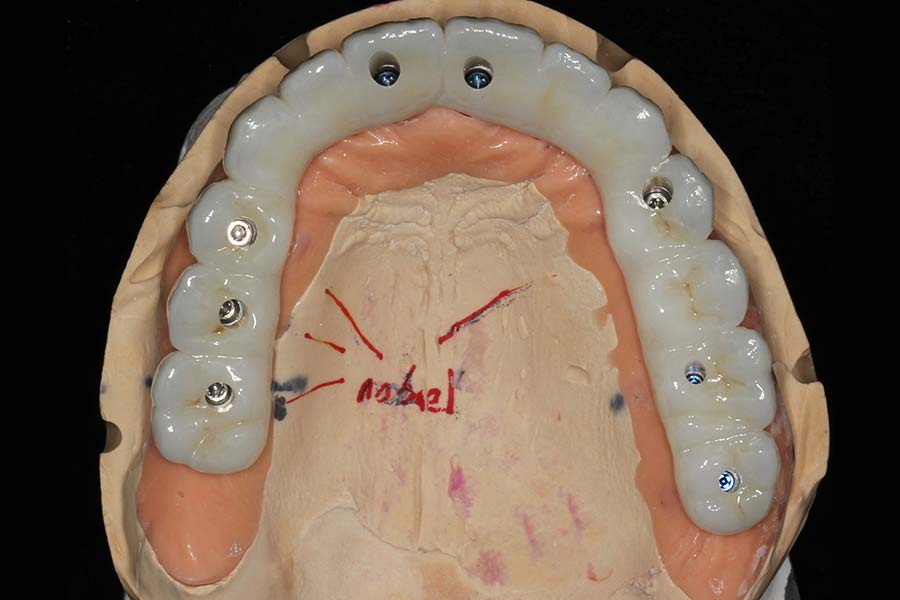

Smile GalleryImplant RestorationsFull Mouth Implant Restoration Full arch zirconia implant bridge (full smile) 1 of 37 Pre-op full smile Pre-op lips retracted Pre-op panoramic x-ray Extraction of strategic teeth Placement of implants Extraction of some remaining teeth after verification of adequate implant stability Occlusal view Post-op panoramic x-ray Immediately fabricated provisional restoration (tissue side view) Immediately fabricated provisional restoration (occlusal side view) Immediate provisional delivered on day of surgery Immediate provisional 2 weeks later Scalloped tissue developed from the provisional at 2 weeks Jig used for making a master impression Provisional in place (full smile) Provisional in place (lips retracted) Provisional in place (right side) Provisional in place (left side) Wax try-in (full smile) Wax try-in (right side full smile) Wax try-in (left side full smile) Wax try-in (full face, lips together) Wax try-in (full smile) Wax try-in (right side) Wax try-in (left side) Wax try-in (lips retracted) Full arch zirconia implant bridge on master cast (frontal view) Full arch zirconia implant bridge on master cast (occlusal view) Implant positions and soft tissue representation on master cast (occlusal view) Soft tissue representation on master cast (frontal view) Full arch zirconia implant bridge (tissue side view) Soft tissues on day of delivery (occlusal view) Soft tissues on day of delivery (frontal view) Full arch zirconia implant bridge delivered (lips retracted) Full arch zirconia implant bridge (lips retracted, close up) Post treatment panoramic x-ray Full arch zirconia implant bridge (full smile)